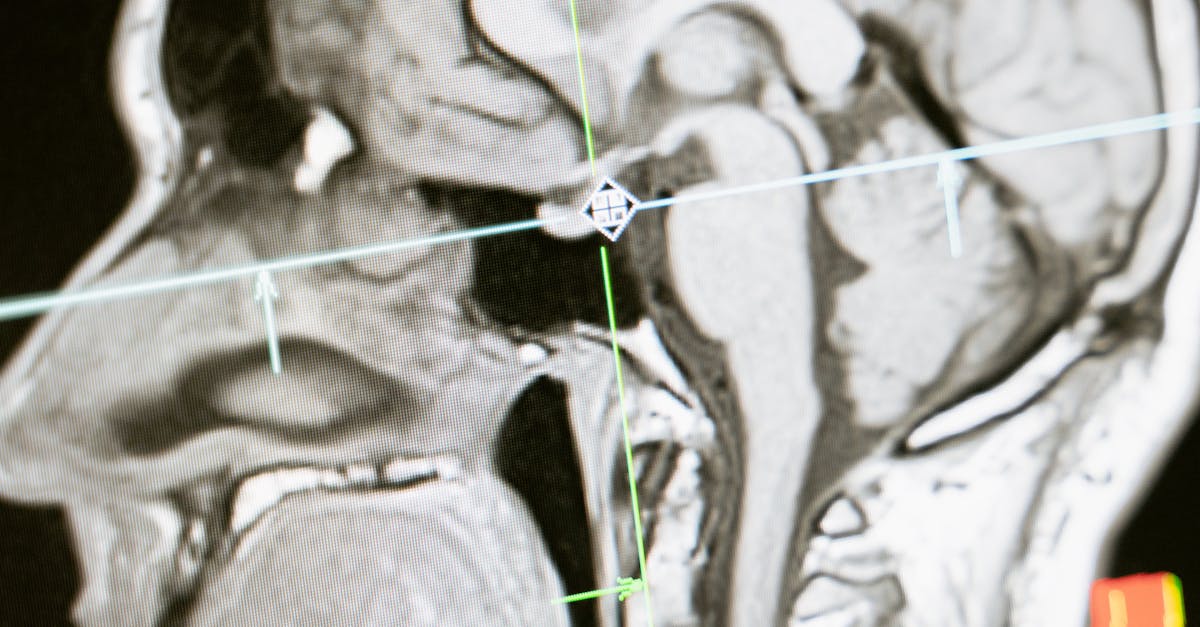

Pour confirmer le diagnostic, il est souvent nécessaire de recourir à des examens d’imagerie. La radiographie, l’IRM et le scanner sont des outils cruciaux pour visualiser les structures rachidiennes. Ces examens permettent de déceler des signes de sténose, tels que des rétrécissements du canal vertébral ou des compressions nerveuses.

- IRM (Imagerie par Résonance Magnétique) : Cet examen est particulièrement utile pour visualiser les tissus mous, y compris les disques intervertébraux et les nerfs. Elle contient des informations précieuses sur la présence de hernies discales ou d’autres anomalies.

Une fois l’examen clinique réalisé, il sera peut-être nécessaire de recourir à des examens d’imagerie. Les deux principales modalités utilisées sont la radiographie et l’IRM. La radiographie permet d’avoir une première idée de l’état des vertèbres et de déceler des anomalies osseuses. Cependant, l’IRM est souvent privilégiée pour un diagnostic plus précis, car elle permet de visualiser les tissus mous, les disques intervertébraux et les nerfs, offrant ainsi une vue d’ensemble complète de la sténose.